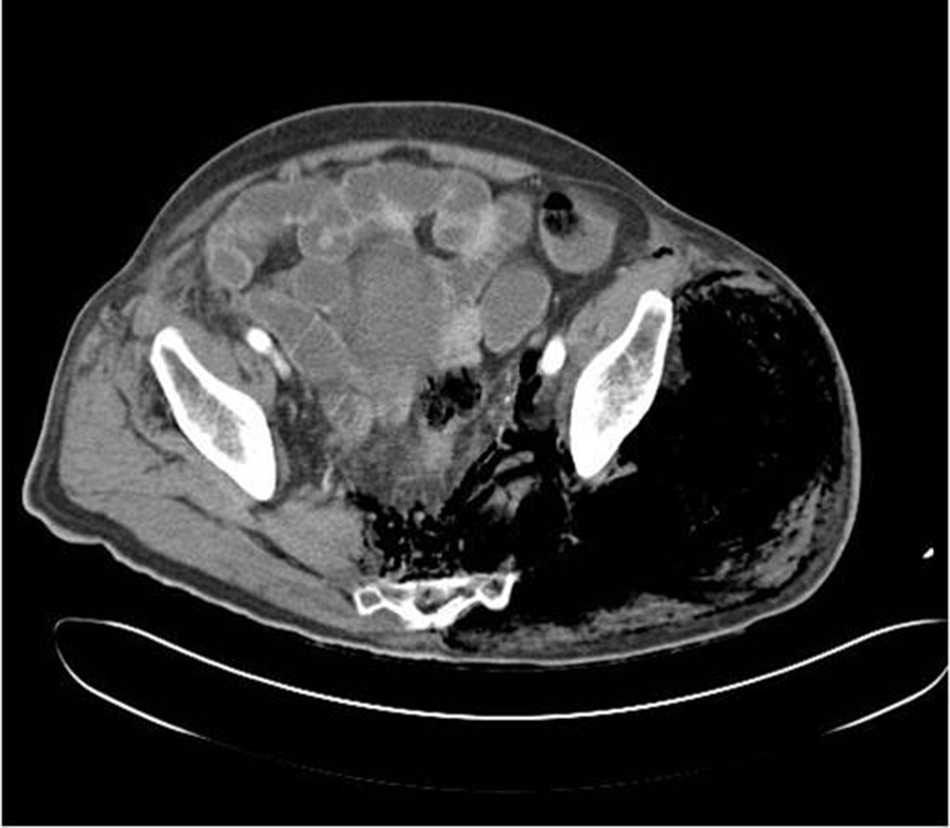

Se realiza TC abdominopélvico y de extremidades inferiores (fig. 1) que muestra: dilatación severa de asas intestinales con masa a nivel cecal, enfisema subcutáneo en glúteo izquierdo que progresa hasta la rodilla y gas a nivel de la vena cava inferior.